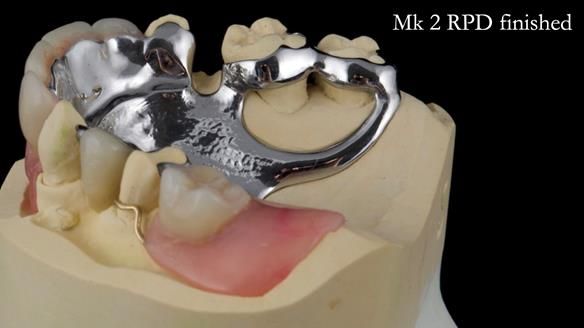

Jean’s Class I Mod III RPD: Learning from My Mistakes – From a Fractured Mk1 to a Stronger Mk2 (4 Years On)

In this edition, I present the removable partial denture treatment for Jean, an 80-year-old woman with a sore mouth caused by a soft tissue-supported 'gum stripper' acrylic denture and a clenching habit. Below, I outline the step-by-step process of her treatment. It wasn't straightforward; I had to remake the denture after it fractured to achieve a satisfactory result. Each patient is unique, and sometimes a new RPD serves as a prototype. Occasionally, I need to make adjustments, learn from any mistakes, and refine the design to get it right.

The treatment has been a success over the past 4 years.